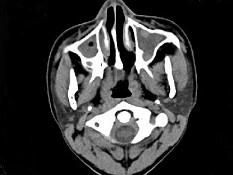

男,14岁,持续性鼻塞、嗅觉减退,流脓涕数年,CT检查如图,最可能的诊断为 ( )

• A.鼻炎及鼻窦炎

• D.鼻及鼻窦息肉

答案: A